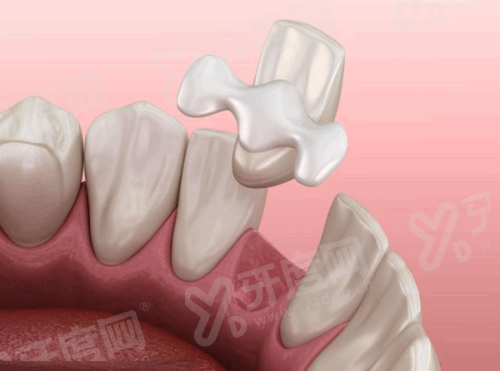

2、邵阳雅贝康口腔医院采用数字化种植技术,通过3D导板导航进行种植手术,手术创伤小、修复快,大大减轻了患者的痛苦,让种植牙过程更加舒适。